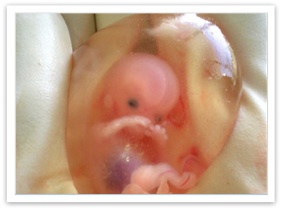

| What is a miscarriage? | ![]()